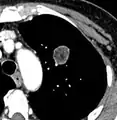

Calcifications and popcorn-like appearance, conferring a diagnosis of hamartoma.[9]

• In case of calcifications, a popcorn-like appearance indicates a hamartoma, which is benign.[3]